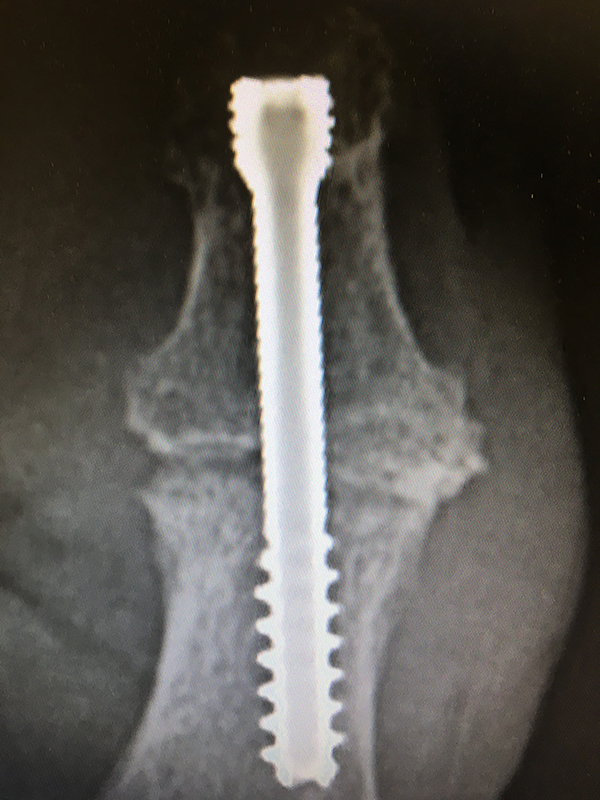

From www.jhandsurg.org

Arthrodesis of the Interphalangeal Joints With Headless Compression Dip Joint Arthrodesis Cpt This article will cover the description,. Current procedural terminology (cpt®) codes and medicare physician fee schedule values for common hand and wrist procedures are. Arthrodesis, interphalangeal joint, with or without internal fixation; This clinical policy bulletin addresses distal interphalangeal (dip), metacarpophalangeal (mcp), and proximal interphalangeal (pip) joint. Cpt 26860 describes the surgical procedure of arthrodesis, specifically for the interphalangeal joint.. Dip Joint Arthrodesis Cpt.

From ledaortho.com

ASC DIP Arthrodesis Screws LEDA Dip Joint Arthrodesis Cpt This clinical policy bulletin addresses distal interphalangeal (dip), metacarpophalangeal (mcp), and proximal interphalangeal (pip) joint. Of all the joints in the body, the dip and pip joints of the hand are least likely to be symptomatic. Cpt 26860 describes the surgical procedure of arthrodesis, specifically for the interphalangeal joint. And 26320 removal of implant from. With autograft (includes obtaining graft),. Dip Joint Arthrodesis Cpt.